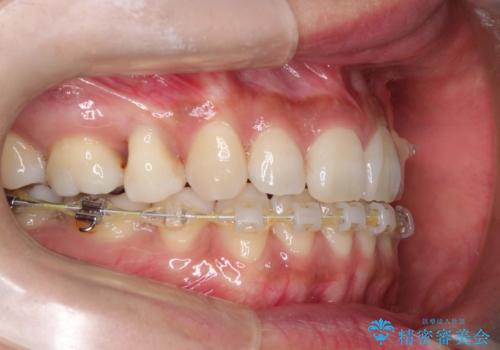

ハーフリンガル抜歯矯正 八重歯を改善する

- ハーフリンガル

- 小臼歯4本抜歯によるハーフリンガル・ワイヤー矯正を計画した。